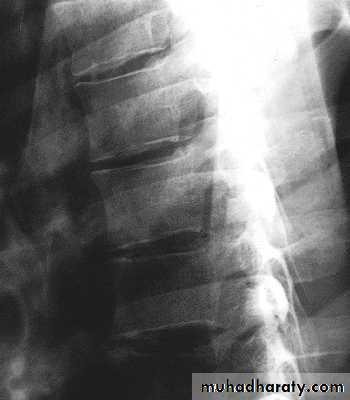

Thoracic Spine X Ray

Lateral radiograph

A/P radiographIn general a typical vertebra consists of :

Curvature is Kyphosis

Gradual increase in sizeof vertebrae from top to bottom

Facets are aligned

horizontally

Articulate with ribs

Rigid